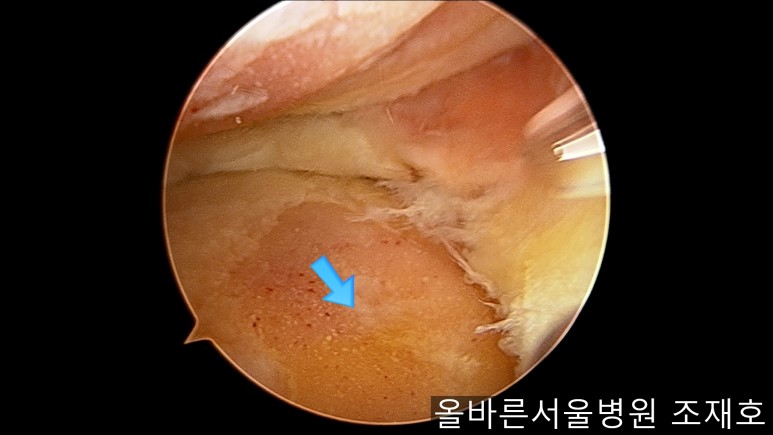

为了软骨再生,在胫骨上端进行微骨折术。

胫骨上端是通过微骨折术,可再生软骨的地方。

尽量将孔打地细密,确认此处骨髓腔内的血流出。